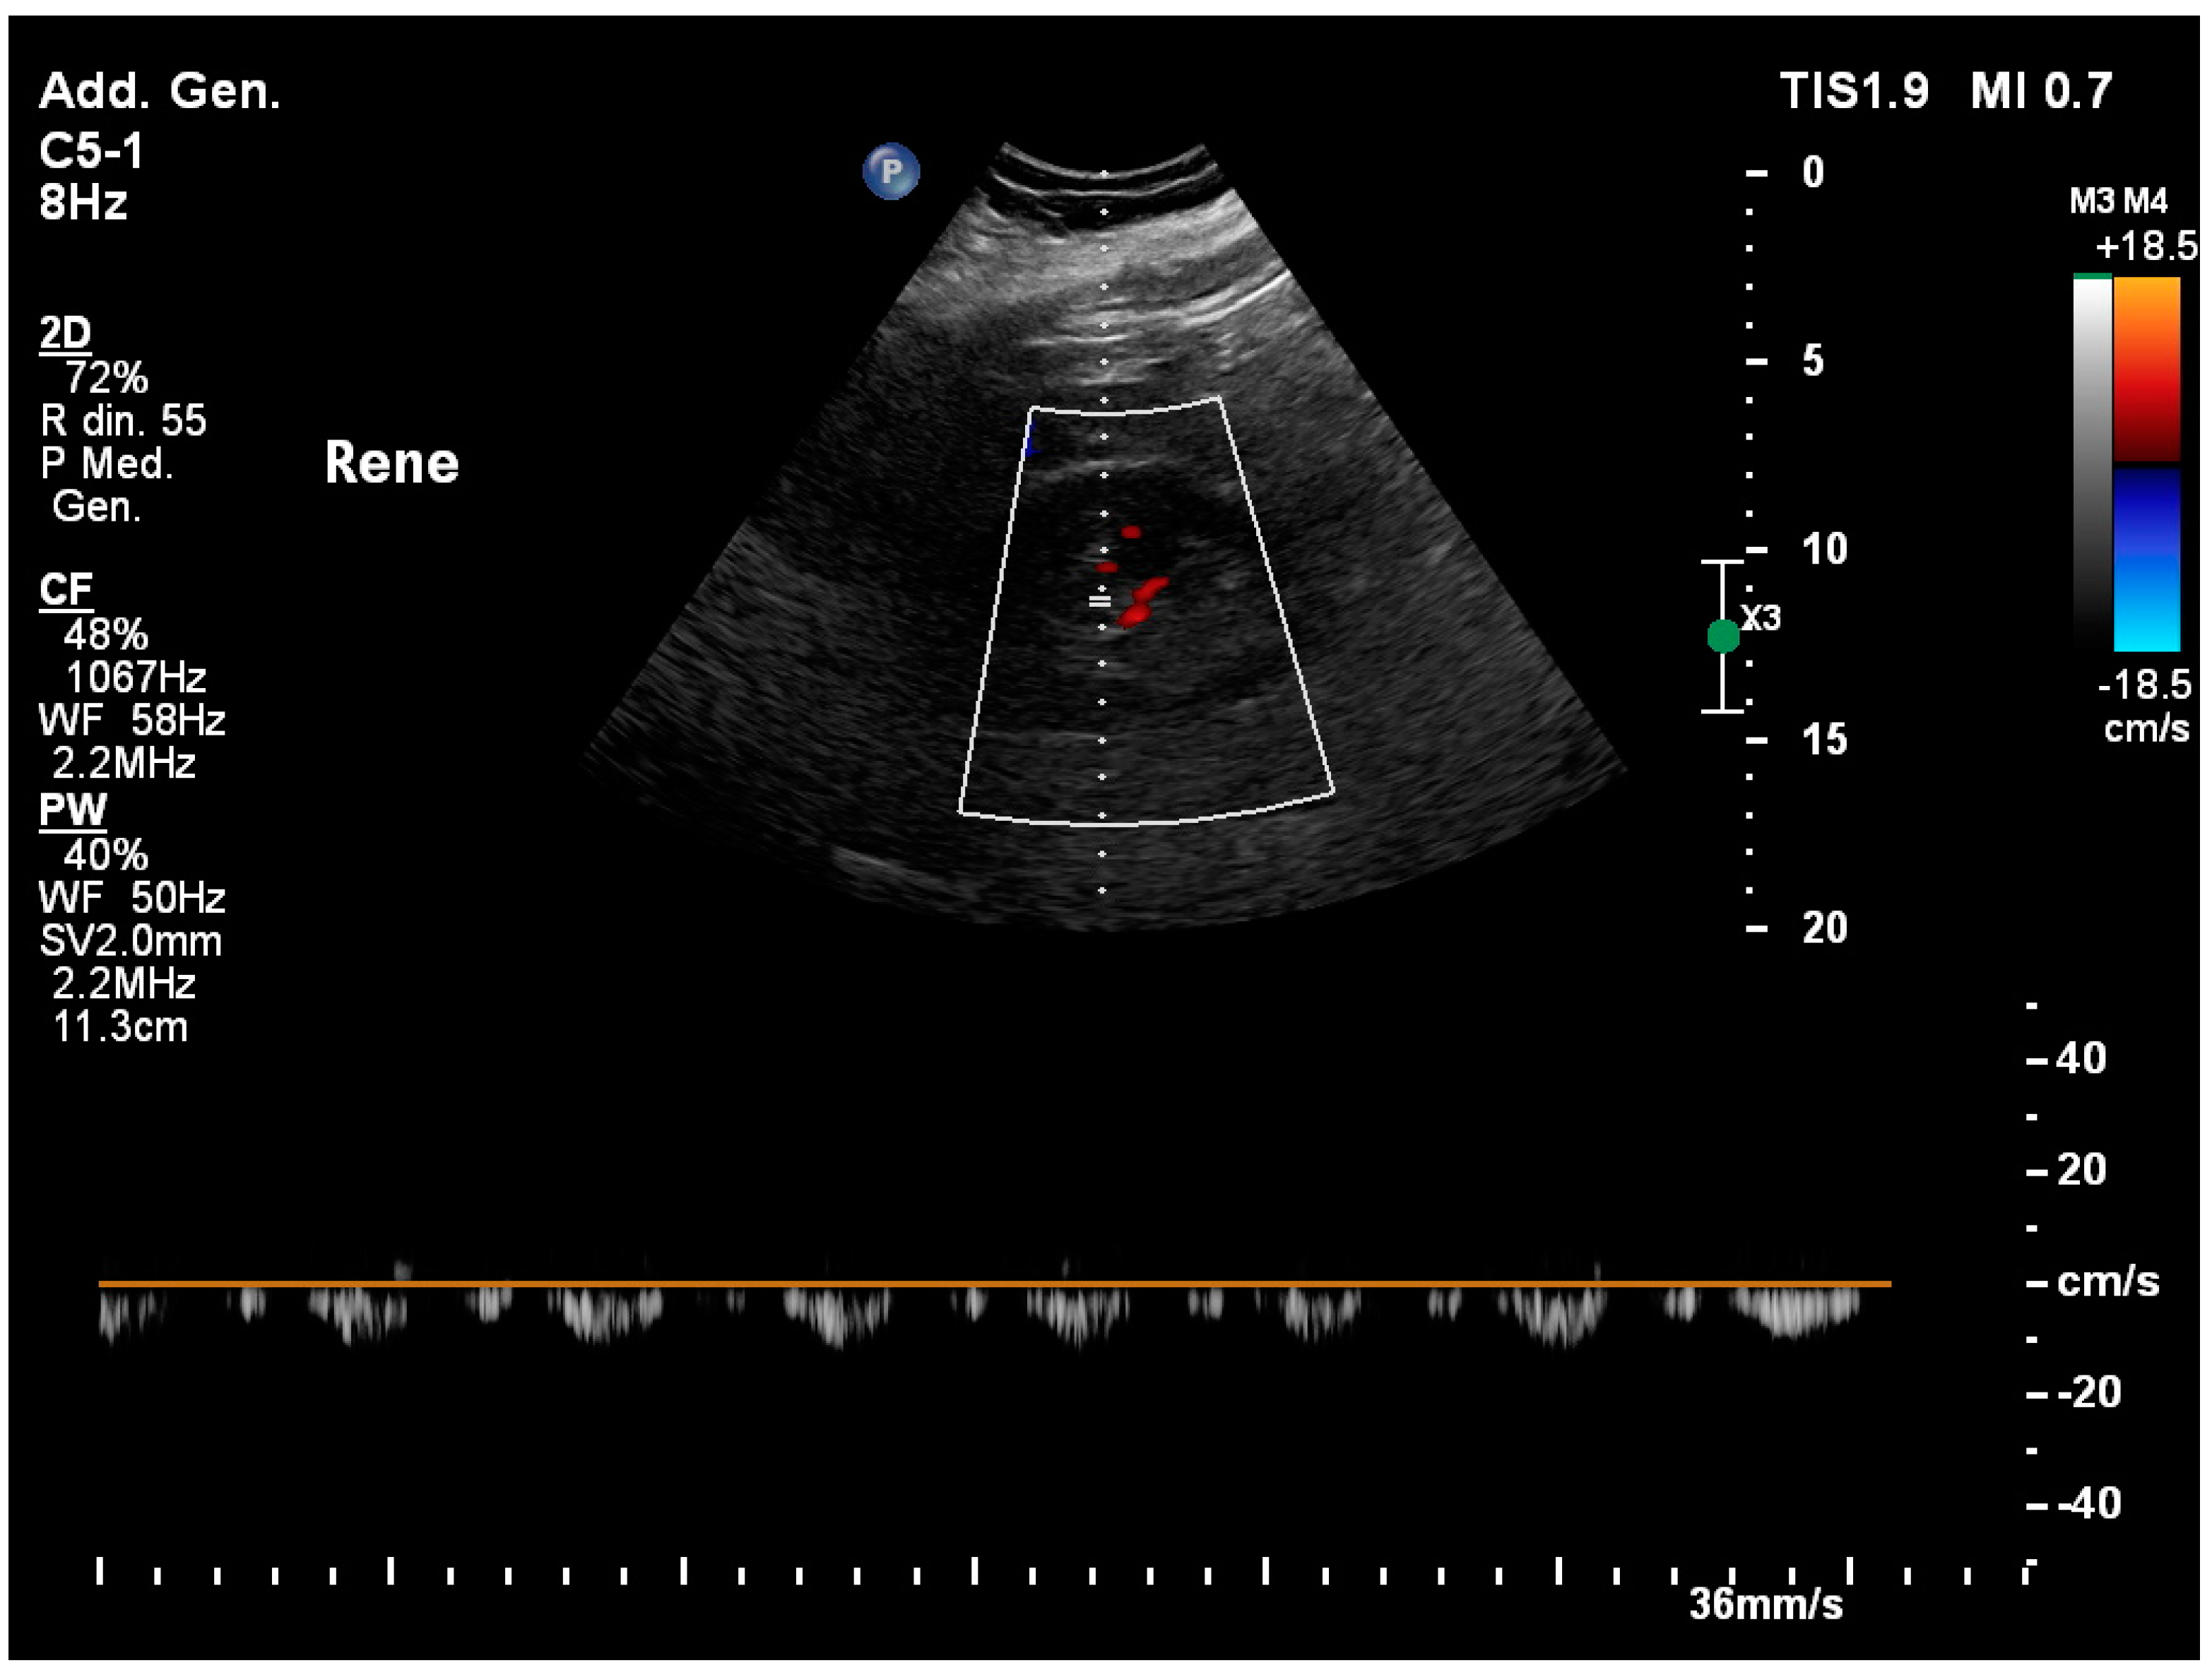

3.13. Renal Resistivity Index

3.2. Acute Kidney Injury